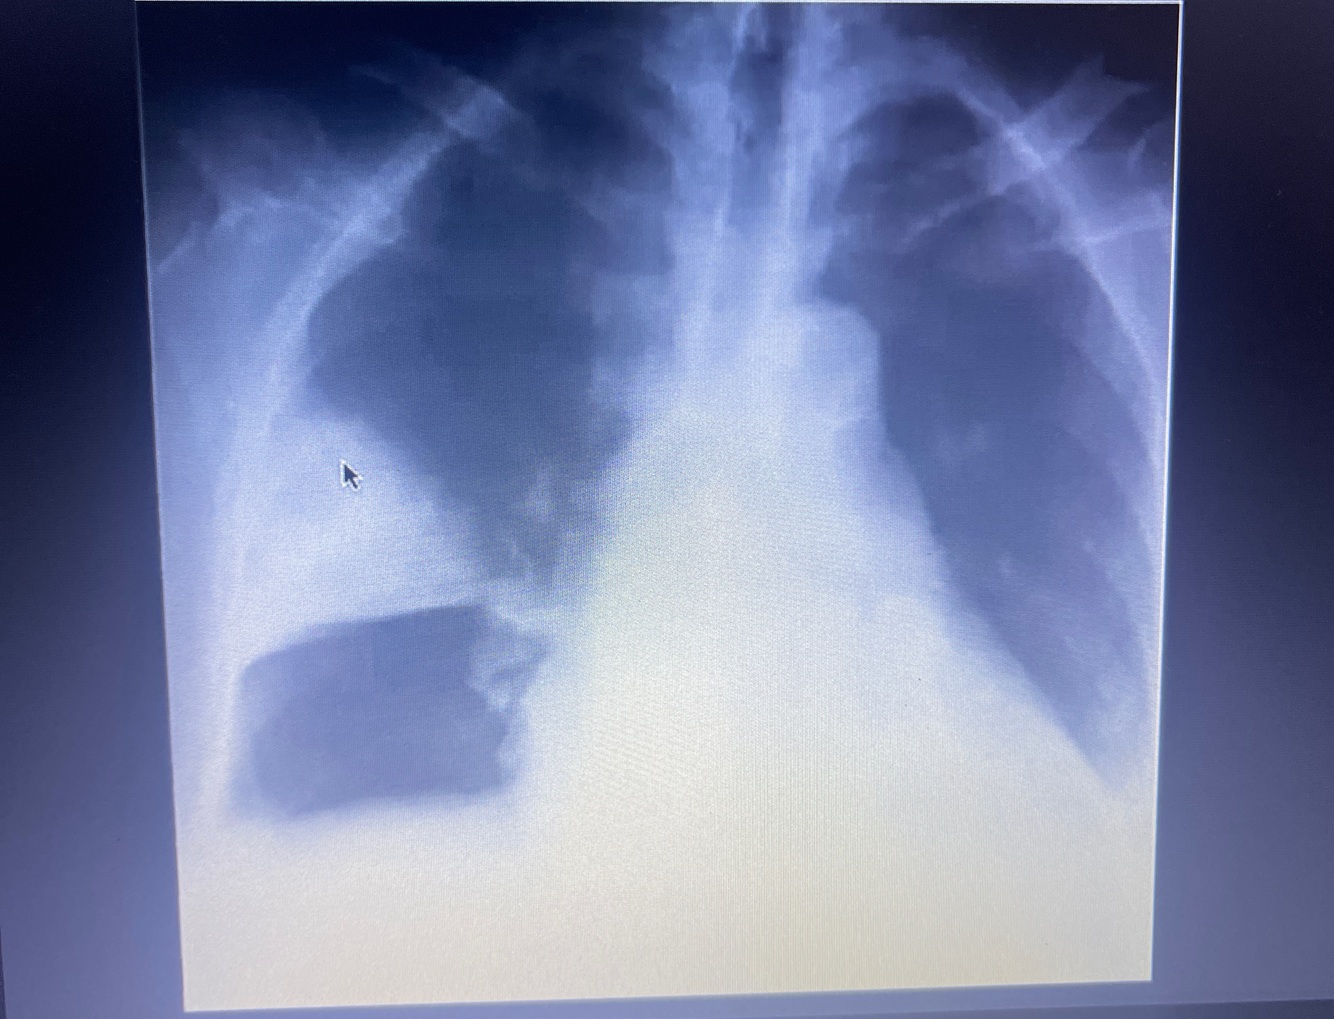

Rx de Tórax

Sinal de WESTERMAK

Diminuição da trama vascular, oligoemia ou seja hipodensidade focal, geralmente é triangular

Corcova de Hampton

Ela geralmente é hiperdensa, sugestiva de infarto pulmonar